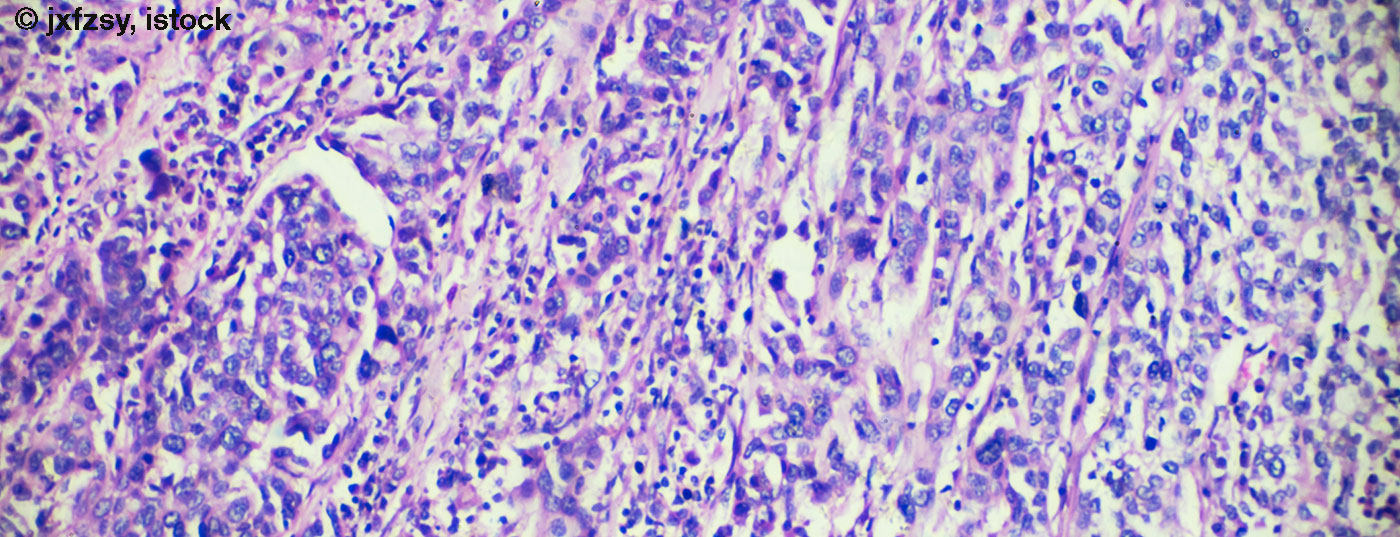

urothelkarzinom_istock

• Fortgeschrittenes Blasenkarzinom

Längeres progressionsfreies Überleben durch Kombinationstherapie

Erste Studienergebnisse weisen darauf hin, dass die Erweiterung der konventionellen Chemotherapie um eine Immuntherapie das progressionsfreie Überleben bei Patienten mit fortgeschrittenem Blasenkarzinom verbessern könnte. Steht ein Paradigmenwechsel ins Haus?